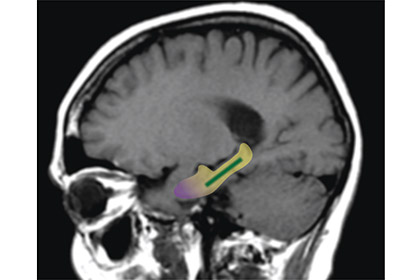

Ученые полагают, что флавонолы улучшают кровообращение в одном из участков мозга, с нарушениями в работе которого ранее уже связывали ослабление памяти — в зубчатой извилине медиальной и нижней поверхности полушария большого мозга. «Если в начале исследования у участников была память типичного шестидесятилетнего человека, спустя три месяца — как у обычного тридцати-сорокалетнего», — утверждает один из авторов статьи Скотт Смолл (Scott A. Small). Однако полученные выводы необходимо проверить в более крупномасштабном исследовании, отметил ученый.